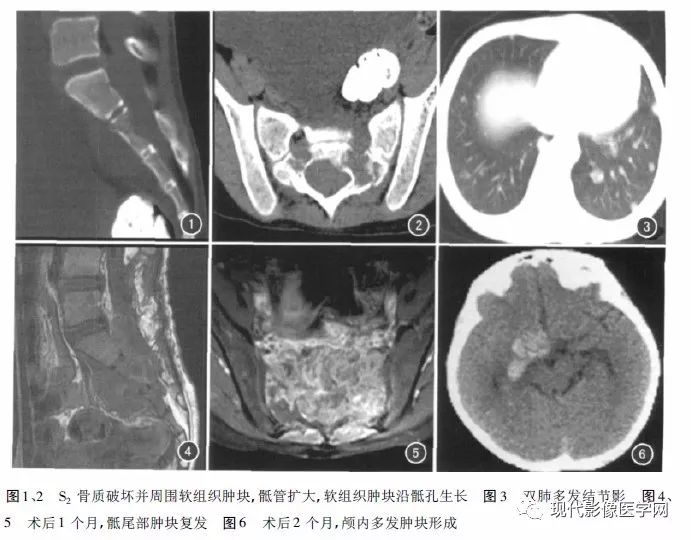

附3例椎管内PNET(来自文献)